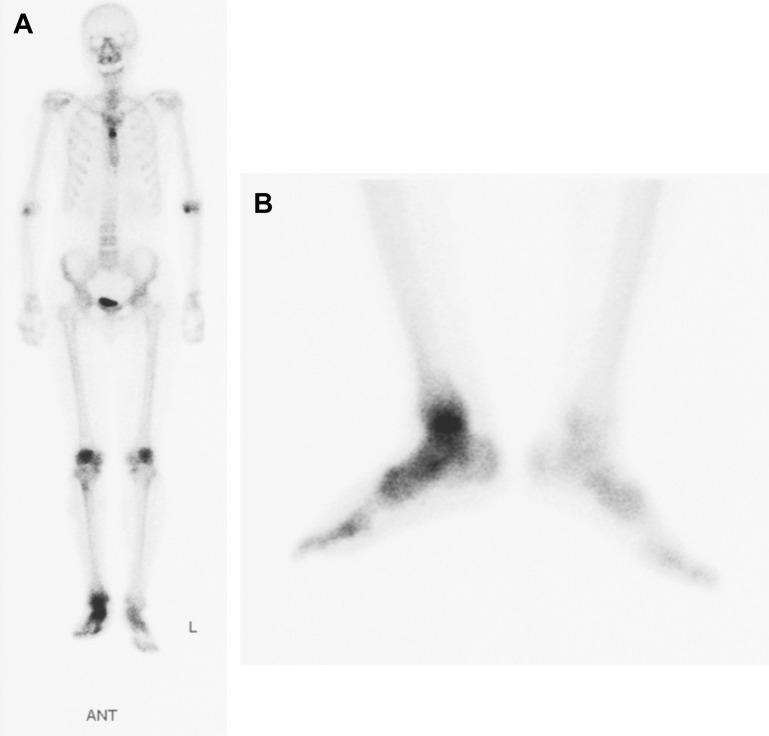

Avascular necrosis tends to occur in the talus because of poor blood supply caused by the extended coverage to the articular cartilage on its surface. Treatment is conservative in the earlier stage of this disease; however, surgical treatment is usually indicated in the advanced stage. Nonunion, leg length discrepancy, or hindfoot instability may occur in patients treated with ankle or tibio-talo-calcaneal fusion. Arthroplasty using a customized total talar prosthesis designed using the computed tomography image of contralateral talus has the potential advantages of weightbearing in the earlier postoperative phase, prevention of lower extremity discrepancy, and maintenance of joint function.